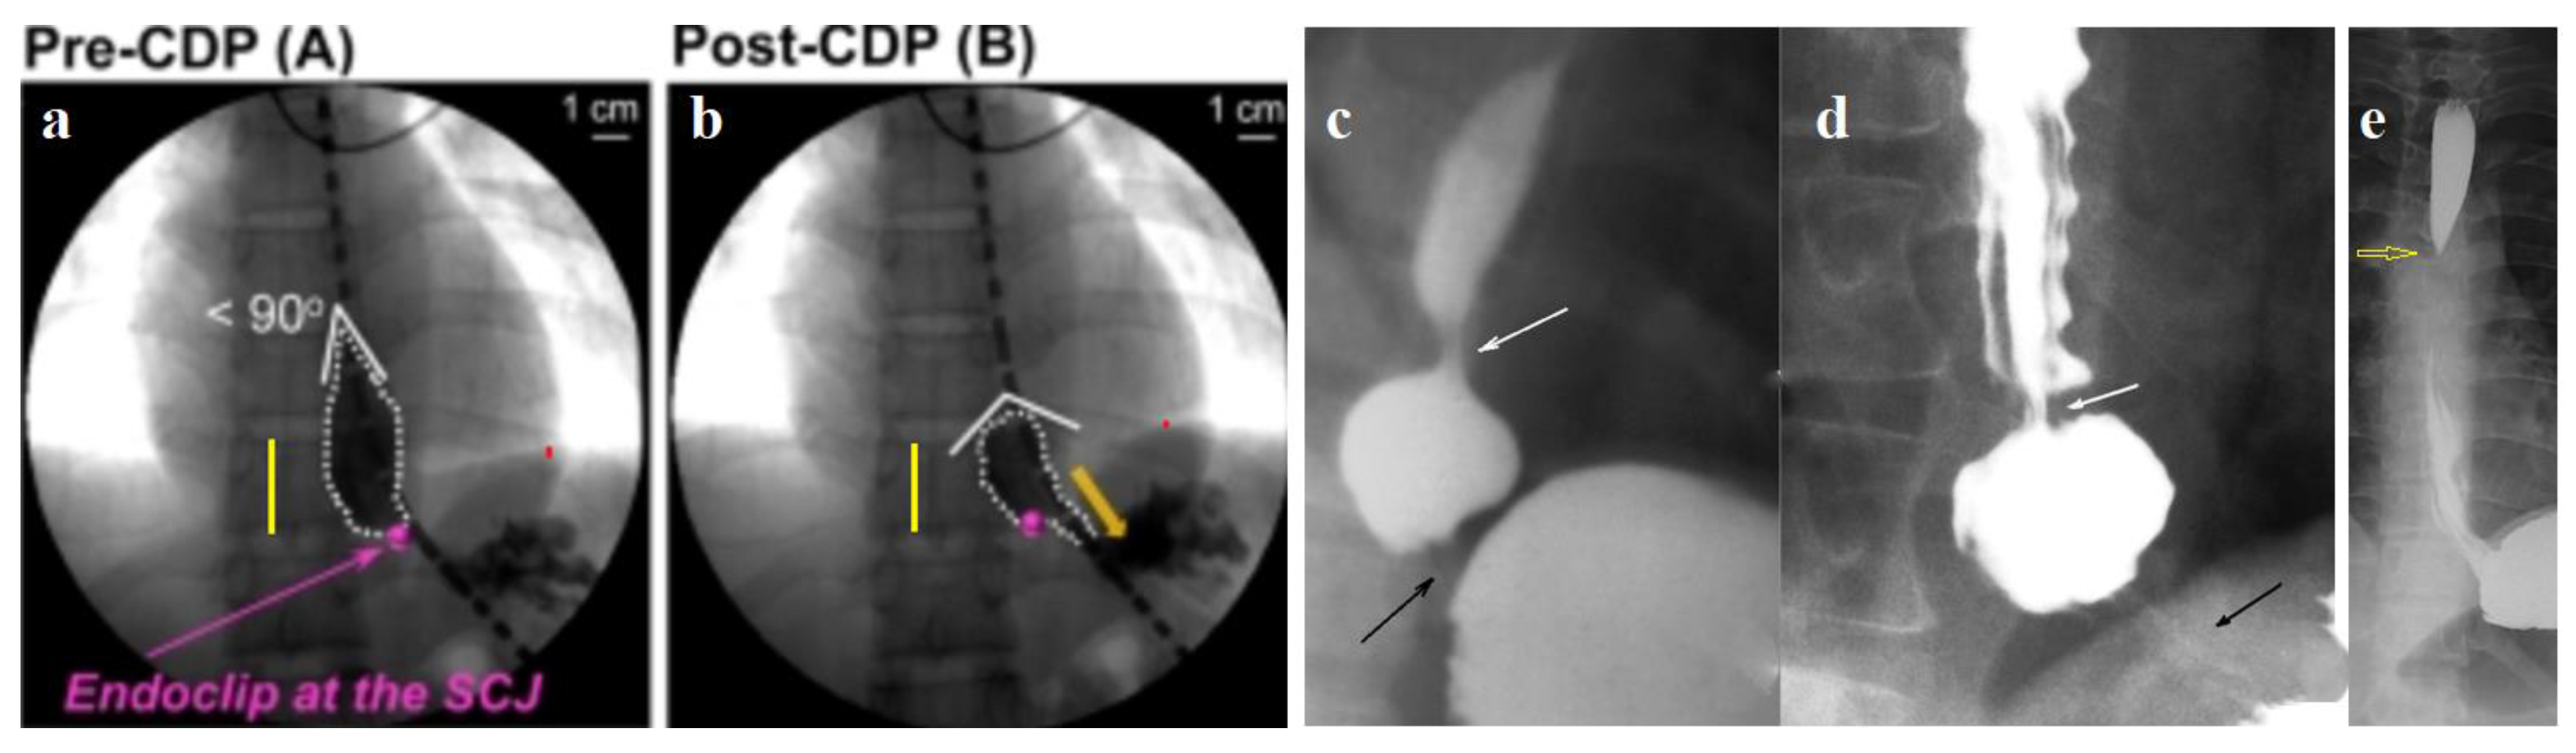

- I have proven the appearance of a functional sphincter in GERD. During eating thick foods, its contraction closes the proximal lumen of the ampulla, helping to create high pressure in the ampulla to inject the bolus into the stomach. It also contracts to prevent reflux above the ampulla. This proximal sphincter (PS) is 5–7 cm long [42]. Over time, it turns into a fibrous ring of different diameters. In some patients, PS turns into a narrow fibrous ring that impairs passage along the esophagus. This is the so-called Schatzki ring [42,50].

- I have proven the appearance of another functional sphincter, which is often observed in non-esophageal manifestations of GERD. This sphincter is in the area of the aortic narrowing of the esophagus. That’s why I called it the aortic sphincter of the esophagus (ASE). Its contraction prevents reflux of the chyme into the upper esophagus and pharynx.